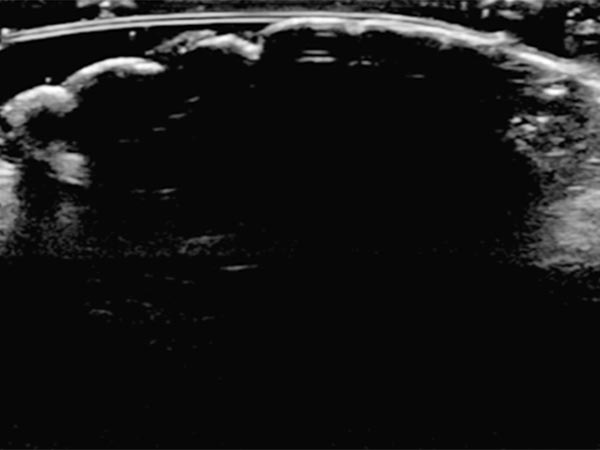

In sonography (B-scan), a total echo reflection with a pronounced acoustic shadow is found due to the high proportion of connective tissue on the surface of the nevus. The lesion itself cannot be visualized.

Color-coded duplex sonography also shows total echo reflection. No perfusion detectable even with a very sensitive setting for blood flow (6 cm/s).

In ultrasound elastography, the lesion codes hard (blue) reflecting the high tissue hardness.